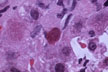

Mallory bodies: H&E stain

Fig 29 - MALLORY BODIES: Chains of sharply defined cytoplasmic globules mostly surrounding the nucleus in an enlarged,ballooned clear cell. They are composed of masses of intermediate keratin filaments from cytoskeleton Irregular in size and shape.They are demonstrable by H&E,Mallory stains and by immunostains for keratin.By EM three types can be recognizedz:Type I=parallel filaments;Type 2=randomly orientd filaments;Type 3=granular material with some filaments at periphery.Seen in hepatocytes of alcoholics and other conditions, in bile duct eithelium and in alveolar cells in asbestosis. Not diagnostic for any specific disease.It is postulated that the collapse of the filaments toward the center makes the cell to expand and undergo necrosis.